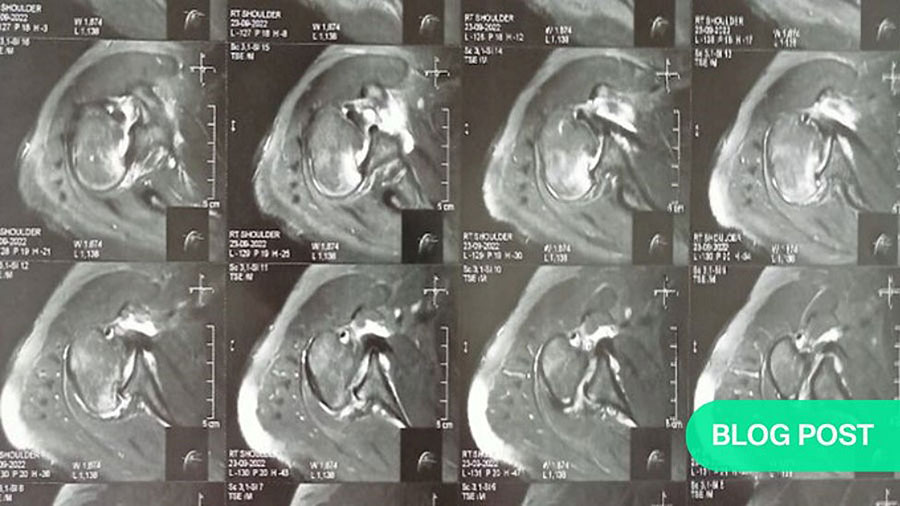

Subsequent CT and MRI scans provided clarity: the shoulder contusion had been a misdiagnosis. Instead, the patient suffered from a locked posterior shoulder dislocation. The locking occurred between an anterior defect in the humeral head, known as a reverse Hill-Sachs lesion, and the posterior glenoid rim.